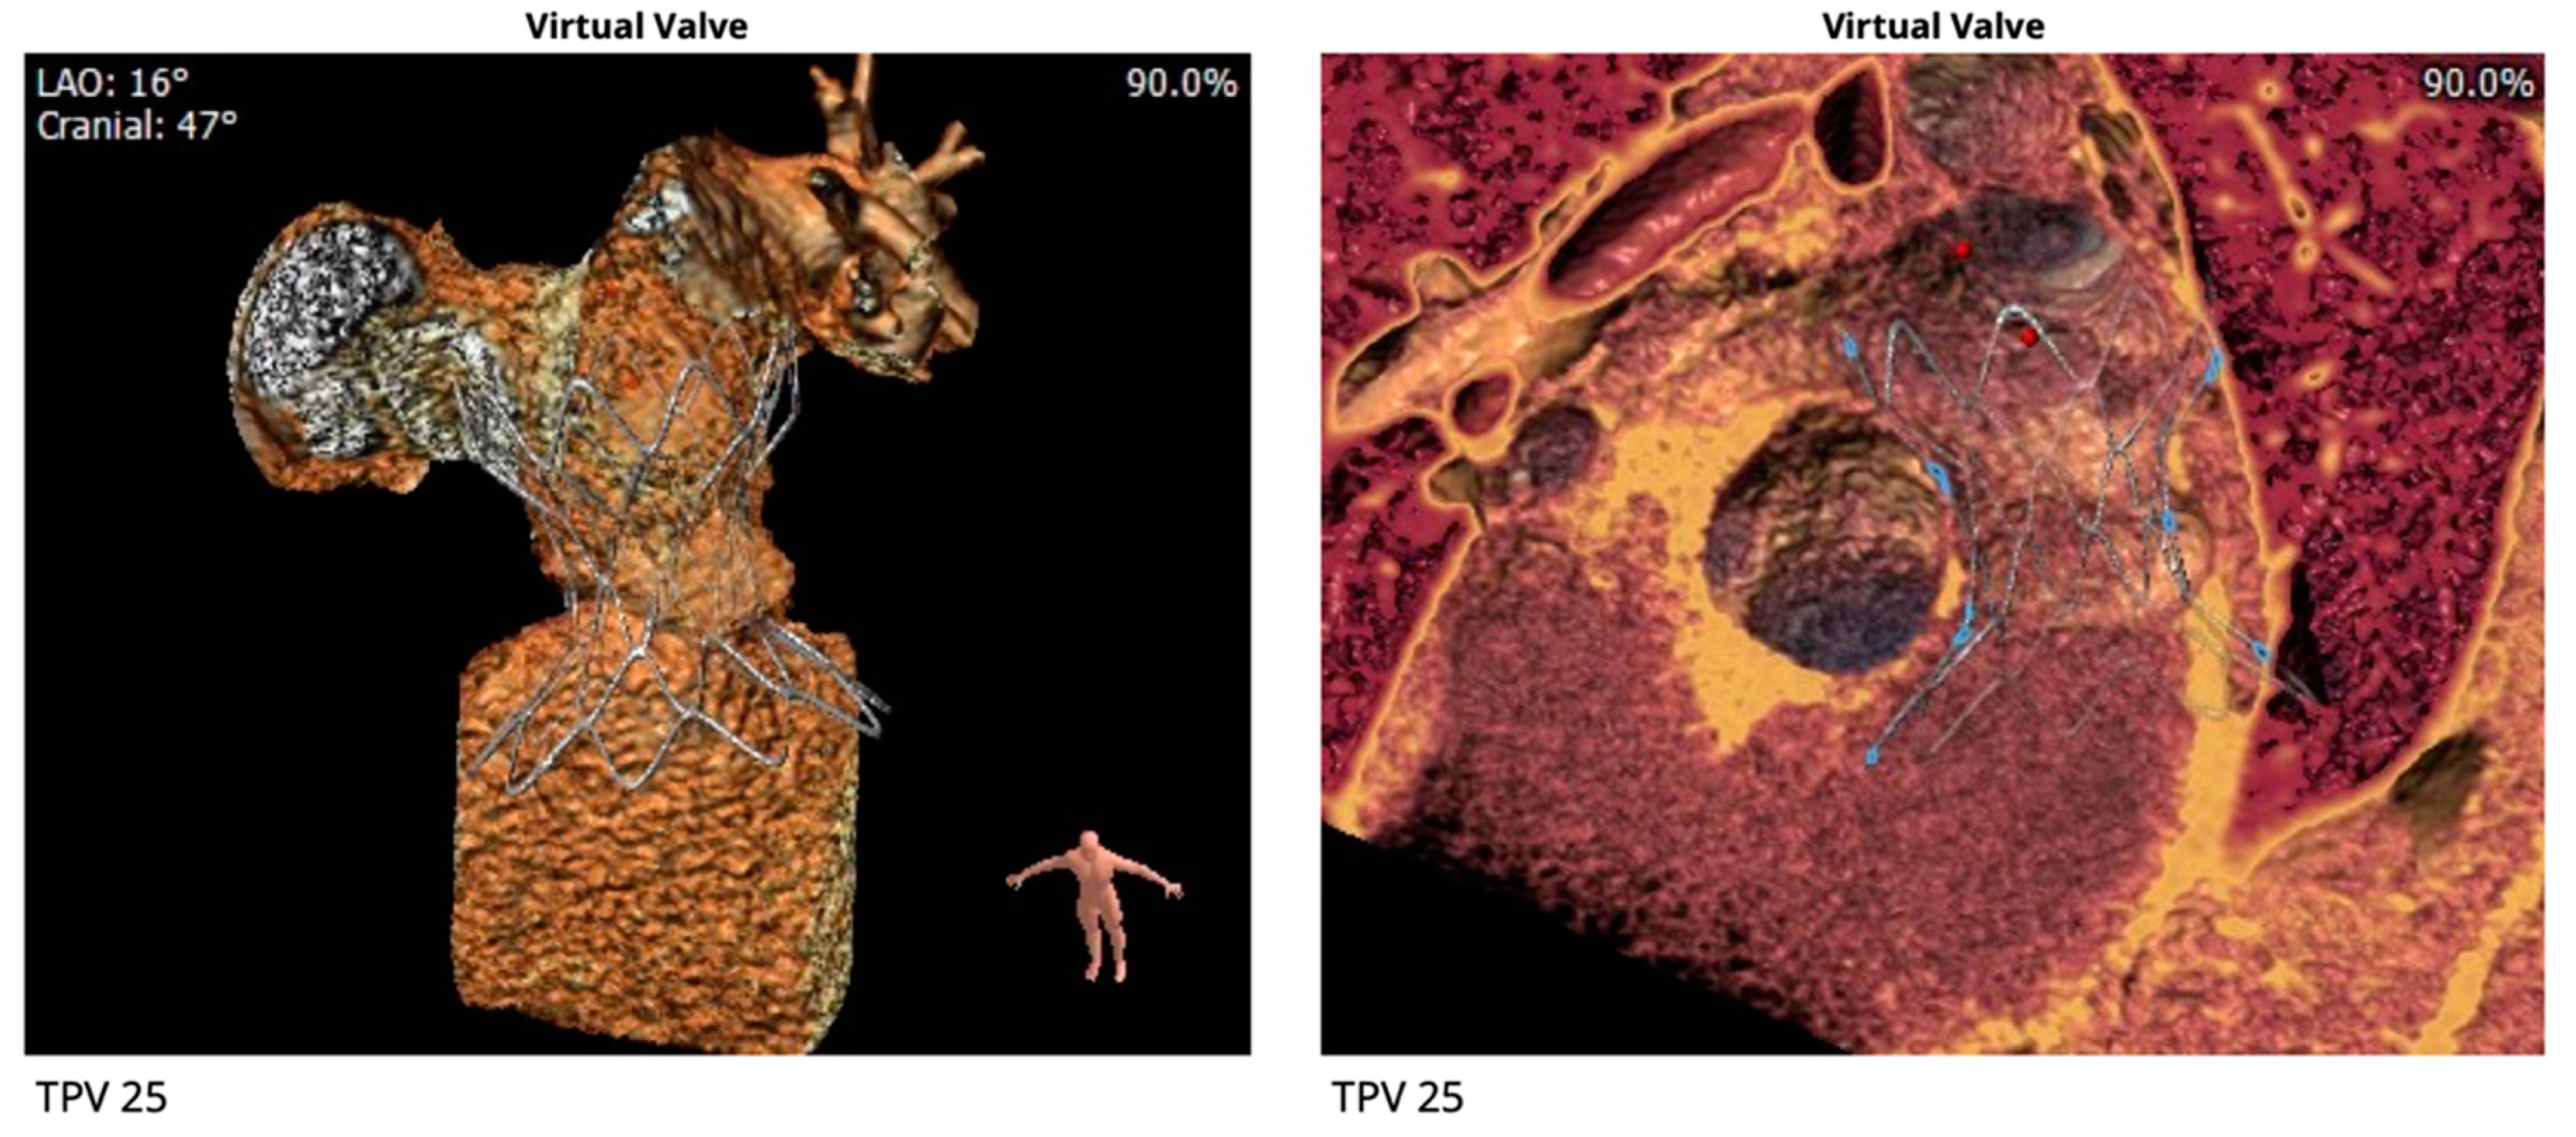

2.3. Percutaneous Pulmonary Valve Placement

- Tandon, A.; Burkhardt, B.E.; Batsis, M.; Zellers, T.M.; Forte, M.N.V.; Valverde, I.; McMahan, R.; Guleserian, K.J.; Greil, G.F.; Hussain, T. Sinus Venosus Defects: Anatomic Variants and Transcatheter Closure Feasibility Using Virtual Reality Planning. JACC Cardiovasc. Imaging 2018, 12, 921–924. [Google Scholar] [CrossRef] [PubMed]